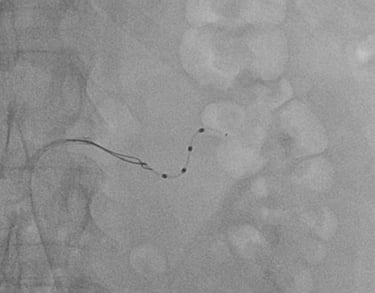

CORONAROGRAFIA

La Coronarografia è l’esame piu’ approfondito per valutare la presenza di restringimenti (“stenosi”) a carico delle arterie coronarie, ovvero delle arterie che nutrono il cuore. Viene effettuata tramite utilizzo di appositi cateteri che vengono inseriti attraverso l'arteria radiale o femorale. Per acquisire le immagini viene utilizzato un liquido chiamato “mezzo di contrasto” che opacizza il lume delle arterie mescolandosi al sangue. Le immagini vengono acquisite da un macchinario che emette una debole radiazione e registra le immagini.